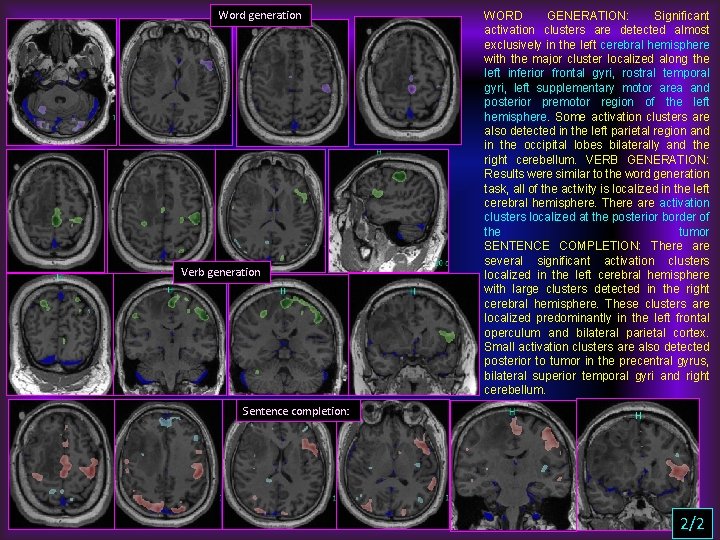

Word generation Verb generation WORD GENERATION: Significant activation clusters are detected almost exclusively in the left cerebral hemisphere with the major cluster localized along the left inferior frontal gyri, rostral temporal gyri, left supplementary motor area and posterior premotor region of the left hemisphere. Some activation clusters are also detected in the left parietal region and in the occipital lobes bilaterally and the right cerebellum. VERB GENERATION: Results were similar to the word generation task, all of the activity is localized in the left cerebral hemisphere. There activation clusters localized at the posterior border of the tumor SENTENCE COMPLETION: There are several significant activation clusters localized in the left cerebral hemisphere with large clusters detected in the right cerebral hemisphere. These clusters are localized predominantly in the left frontal operculum and bilateral parietal cortex. Small activation clusters are also detected posterior to tumor in the precentral gyrus, bilateral superior temporal gyri and right cerebellum. Sentence completion: 2/2